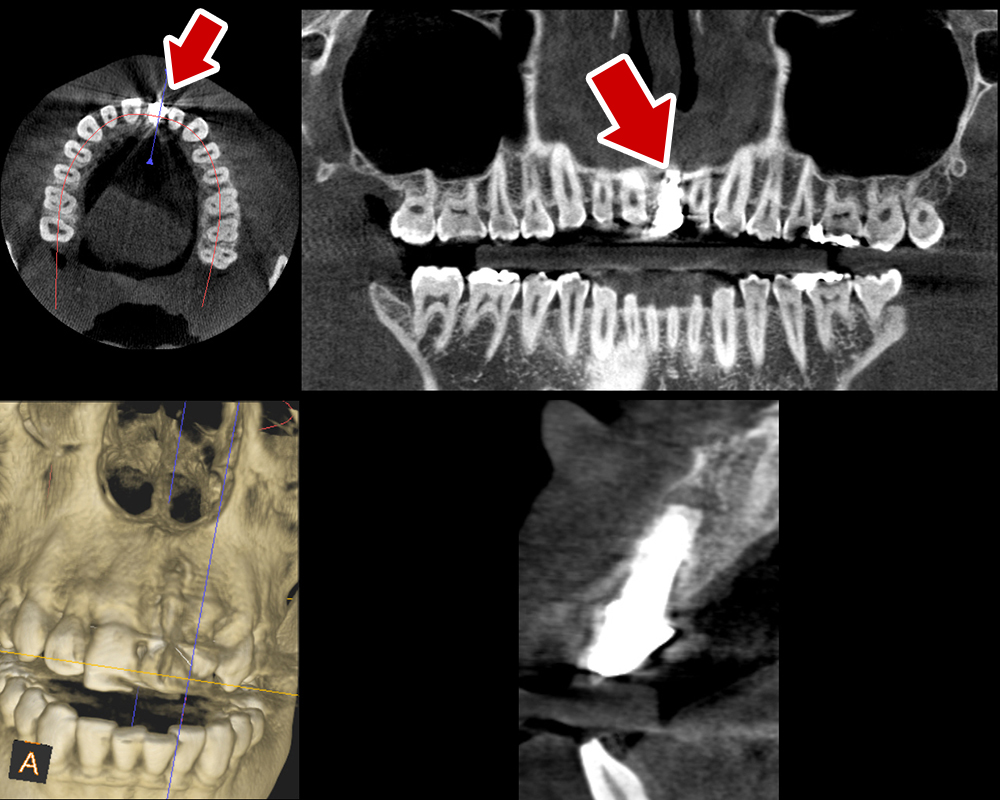

29歳 男性 歯科医療関係者紹介。また、お姉さんが歯科医療関係者。

- 主訴

- 左上1番目の歯が長期にわたり痛く、噛めない。

- 処置内容

-

1本インプラント埋入+再生療法。抜歯即時埋入、即時荷重法⇒抜歯を行い、

同時にインプラント埋入(即時埋入)、そして同時にインプラントへ仮歯を装着(即時荷重)

歯が無い期間なく、社会生活に支障が出ない

- 治療費用

- 約39万円(税込)

- 治療期間

9か月

手術当日に人工歯(仮歯)まで装着。 (通常待機期間は1年必要です。 (抜歯後6か月+インプラント(根)待機期間6か月+仮歯2か月))

- リスク

- 上部構造物、仮歯の破折、術後の腫れ(3日)、人工歯根脱落リスクがあります

- その他

- 学術雑誌、海外公演(アメリカ、ヨーロッパ)に多く紹介されたケース